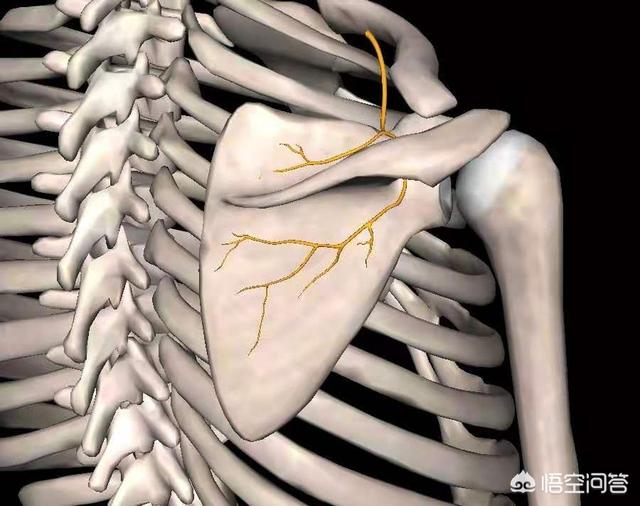

Comme indiqué ci-dessus, ce muscle est anatomiquement ce que l'on appelle un "levator scapulae (anatomie)". Il se développe d'une part sur l'apophyse transverse des vertèbres cervicales 1 à 4, et d'autre part à l'endroit même où se trouve le point douloureux (l'angle supérieur interne de l'omoplate). Sa fonction principale est la suivante :Lorsque la fin du point de douleur est fixéeLa tête et le cou sont inclinés vers l'arrière lorsque les deux côtés sont contractés et raccourcis.Lorsque la tête est baissée pendant une longue période, elle s'étire progressivement lorsque la tête est tirée vers l'avant, jusqu'à ce qu'à la limite, lorsqu'il n'est plus possible de l'étirer davantage, il y ait une douleur à l'angle supérieur interne de l'omoplate, à l'extrémité stationnaire.。

La première raison est quePiégeage du nerf scapulaire dorsalRésultat. Le nerf scapulaire dorsal innerve principalement les muscles scapulaire et rhomboïde juste après la naissance.La région du bord médial de l'omoplate est située à l'endroit où s'attache le muscle rhomboïde, comme le montre l'illustration ci-dessous :

La première raison est quePincement du nerf thoracique longLe résultat. Le nerf thoracique long innerve principalement le muscle serratus anterior, juste au-dessus de l'épine dorsale.La localisation de la région médio-latérale de l'angle du sous-scapulaire est illustrée ci-dessous :